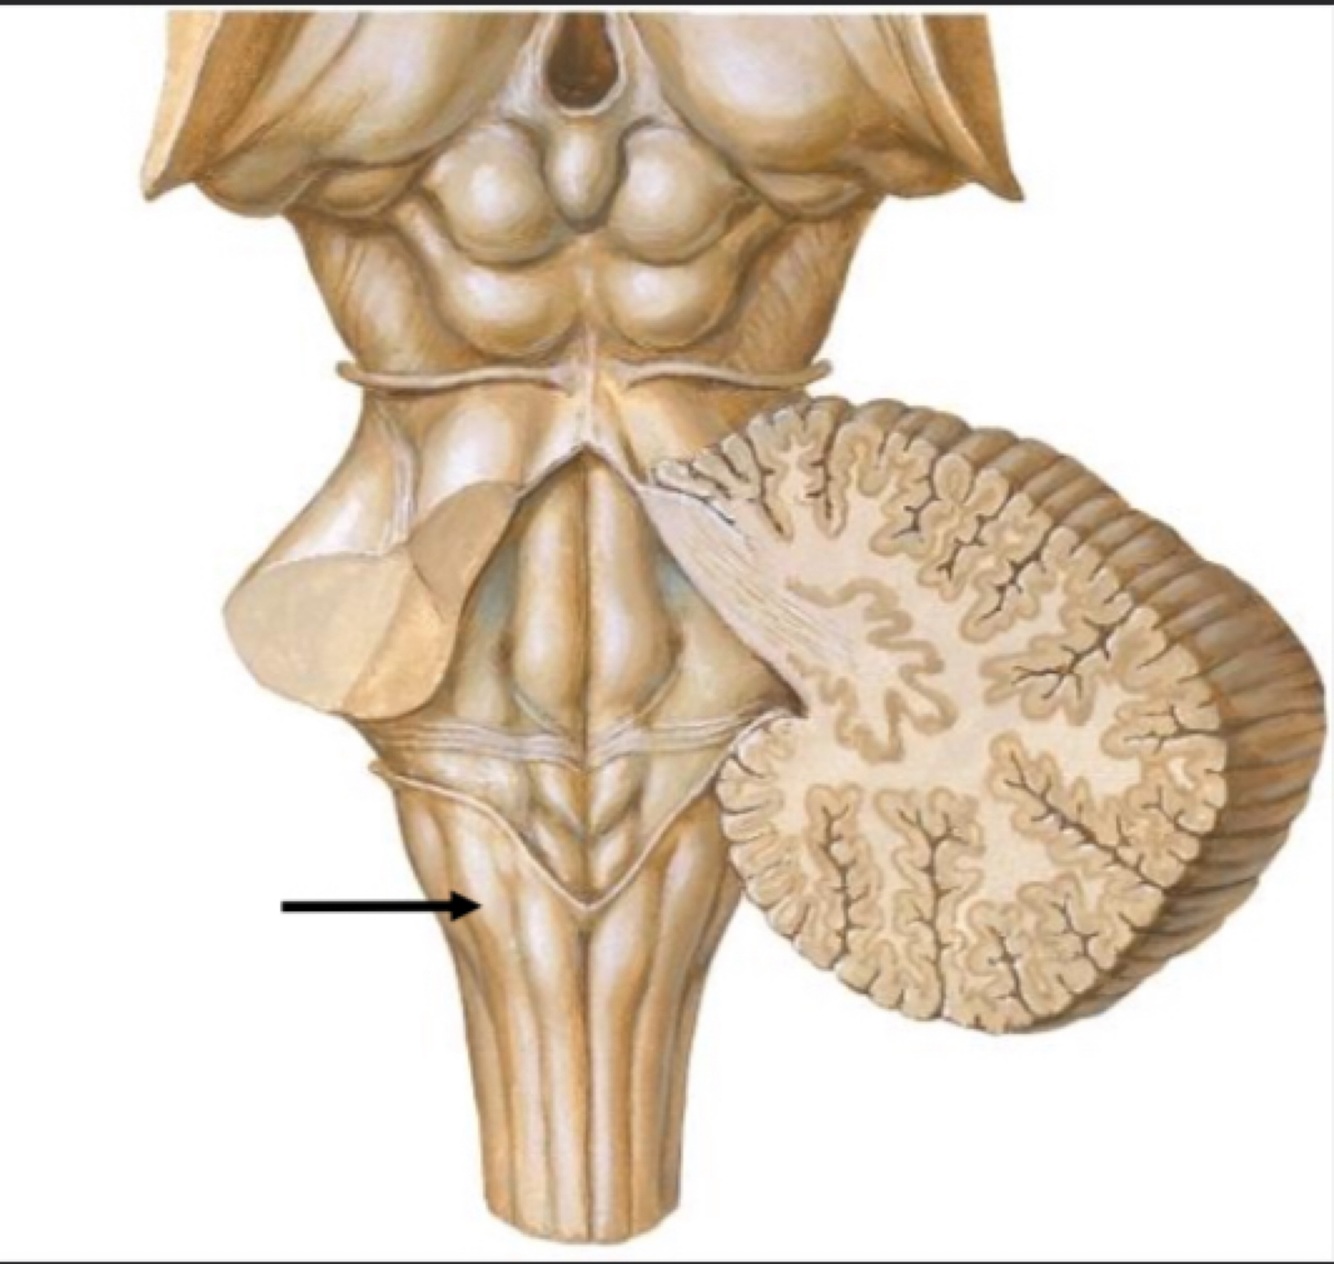

Q

1. Name the structure?

2. What fibers run through this structure?

3. This structure connects which two structures in the CNS?

A

1. Inferior Cerebellar Peduncle

2. Dorsal Spinocerebellar, axons of inferior olivary nucleus

3. Medulla to cerebellum

How well did you know this?